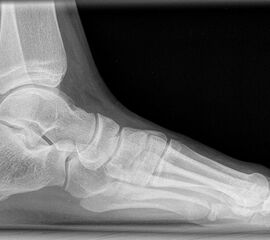

Standard ist die belastete Röntgenaufnahme des Fußes dorso-plantar und seitlich. Günstig ist eine Röhrenkippung von 10°-20°, um die Gelenke der Lisfranc-Linie einsehen zu können.

Ergänzend kann eine Schrägaufnahme hilfreich sein. Bei Metatarsalgien oder Pathologien der Sesambeine liefert die Sprinteraufnahme zusätzliche Informationen. Bei einer Pes planovalgus Fehlstellung wird ergänzend ein Saltzman view durchgeführt.